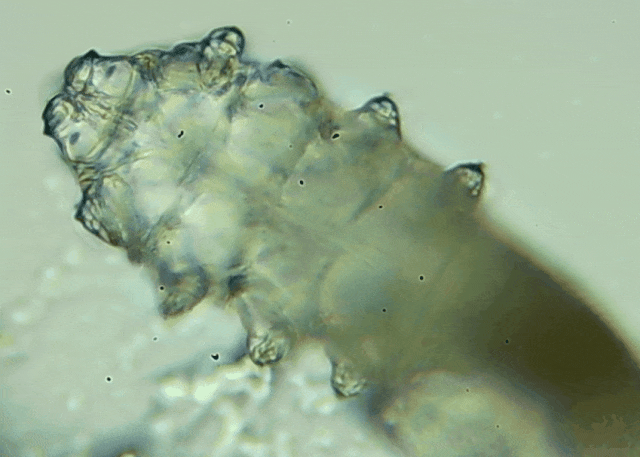

我只是眼睛癢,結(jié)果醫(yī)生說我睫毛里有80只蟲?這不是恐怖片,而是真實(shí)的病例:武漢一13歲男孩,右眼9根睫毛里檢出39只螨蟲,左眼9根里檢出47只。 而且這不是極端個(gè)案,廈門眼科中...

眼瞼位于眼球前面,分為上下眼瞼,而睫毛、一些腺體的開口和淚小點(diǎn)都在眼瞼邊緣,也就是瞼緣上。蠕形螨是一種寄生于毛孔、腺管和瞼緣上的螨蟲,因?yàn)轶w型微小,肉眼無法察覺。...[詳細(xì)]